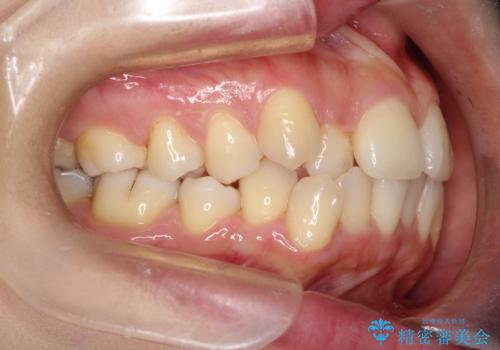

前歯が前後反対にかんでいる インビザラインによる目立たない矯正

- 前歯のかみ合わせを主訴に来院されました。

歯と歯の間をわずかに削り、ガタガタを改善しました。